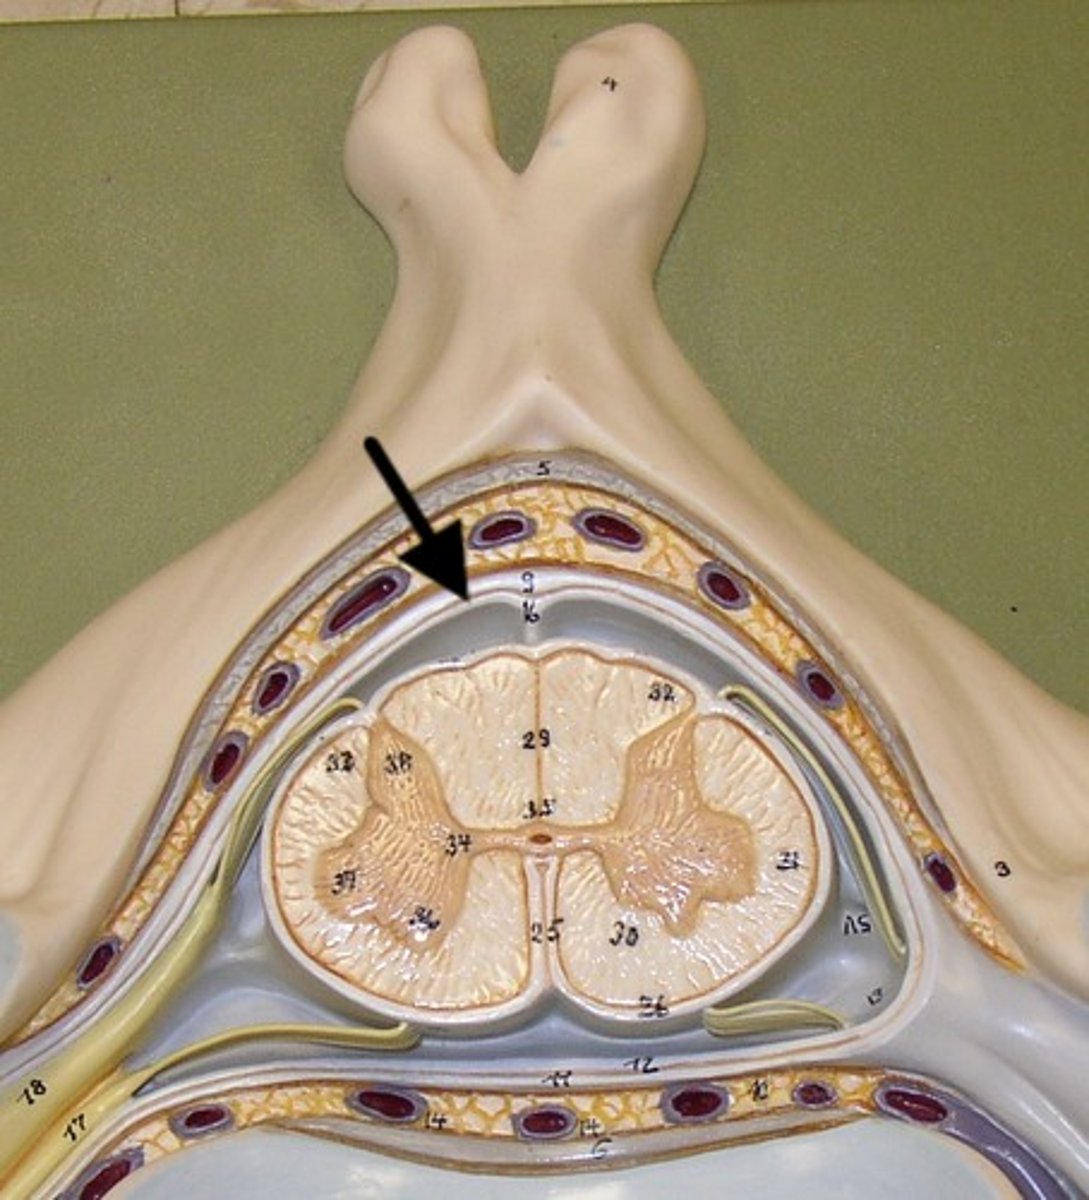

spinal meninges

3 specialized membranes surrounding spinal cord and brain

Stability, shock absorption, carry blood supply (oxygen and nutrients)

3 spinal meninges (Superficial to deep)

dura mater, arachnoid mater, pia mater

Dura mater

tough outer layer of the meninges

arachnoid mater

Made of simple squamous epithelium

Pia mater

thin, delicate inner membrane of the meninges

subarachnoid space

between arachnoid mater and pia mater

filled with cerebrospinal fluid

shock absorber; diffusion of gases, nutrients, etc.

blood vessels for spinal cord

epidural space

space between dura mater and vertebrae

denticulate ligaments

pia mater, through the arachnoid mater, to dura mater

Prevents lateral movement

Lumbar puncture

Withdrawal of cerebrospinal fluid

needle inserted into subarachnoid space between two lumbar vertebrae.

Also known as spinal tap